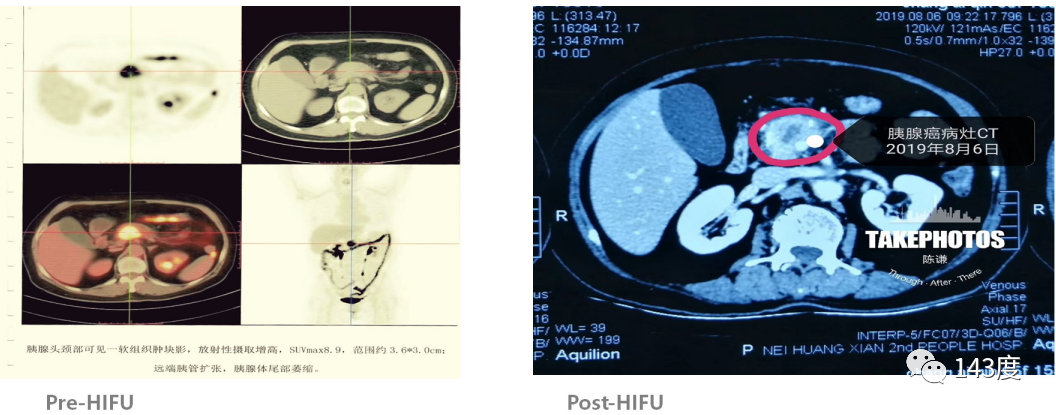

Pancreatic Cancer Treatment Case 5:

Patient: Female, 41 years old, pancreatic cancer

After 9 days of HIFU treatment, a follow-up PET-CT scan showed extensive necrosis at the center of the tumor.